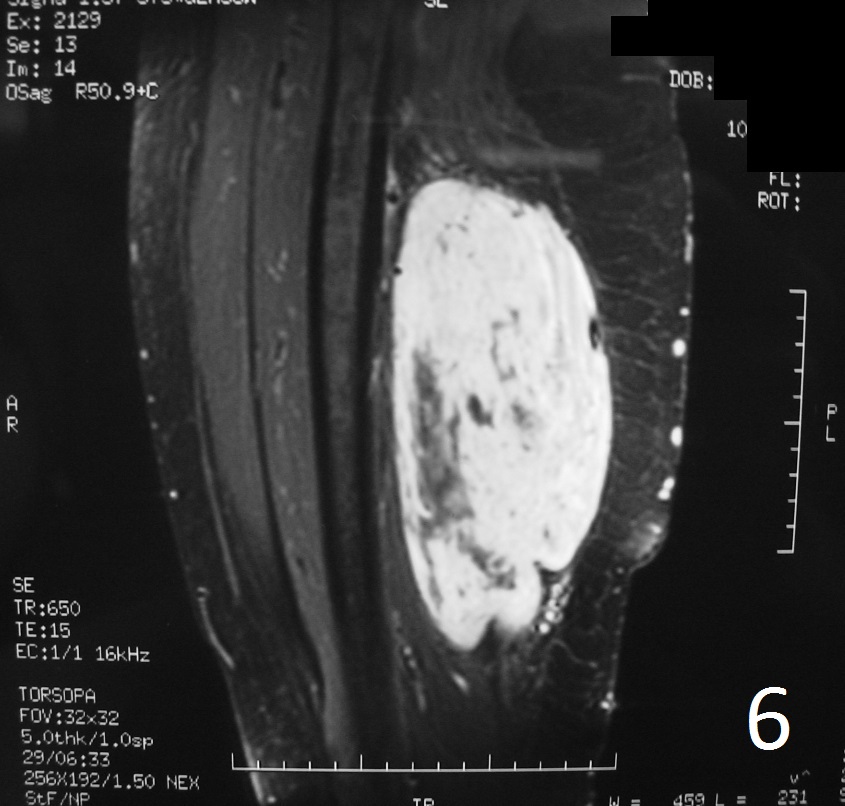

Fig 4-6: T2W FS demonstrates same features (Fig. 4) . Sagittal T1W (Fig. 5) and T1W FS (Fig. 6) of same case.